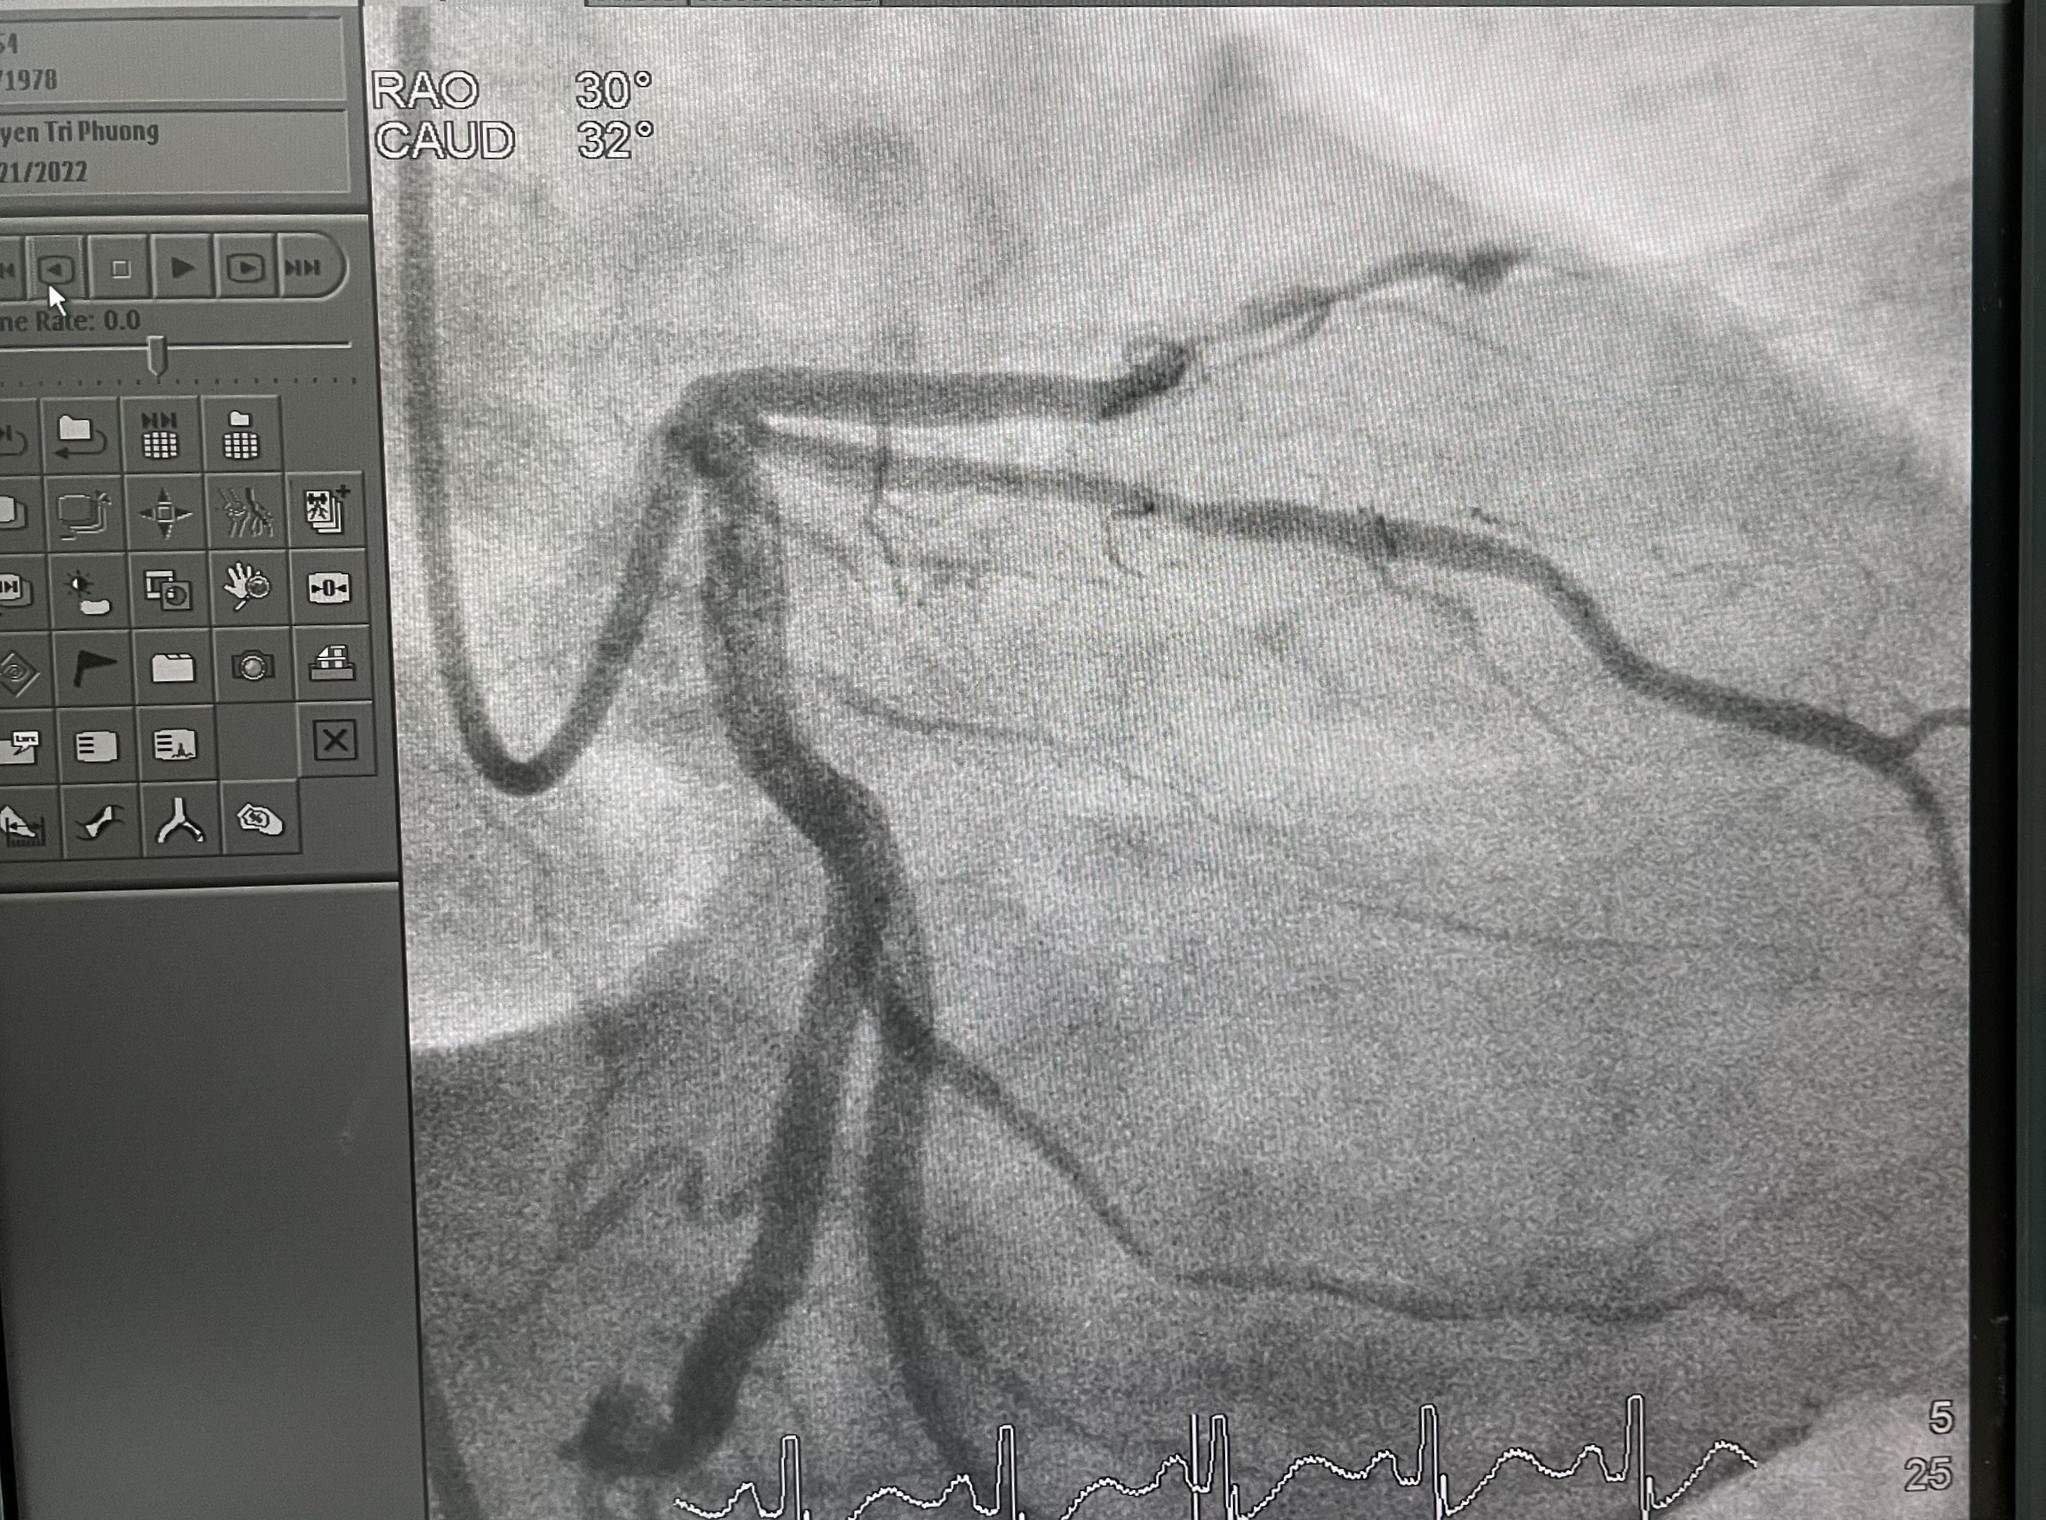

Tại đây, bệnh nhân được chỉ định phải tái thông mạch vành cấp cứu. Kết quả chụp mạch vành cho thấy người bệnh tắc nhánh động mạch liên thất trước (động mạch lớn nhất nuôi tim). Ê-kip đã tái thông bằng cách đặt 1 giá đỡ trong lòng động mạch vành. Thủ thuật kéo dài khoảng 15 phút.

Các bác sĩ nhận định đây là một ca nhồi máu cơ tim cấp, biến chứng ngưng tim ngoại viện đã hồi sức thành công. Kết quả chụp mạch vành cho thấy người bệnh bị tắc nhánh động mạch lớn nhất nuôi tim. Ê-kip can thiệp đã xử lý tái thông, đặt 1 giá đỡ trong lòng động mạch vành, hoàn thành trong 30 phút.